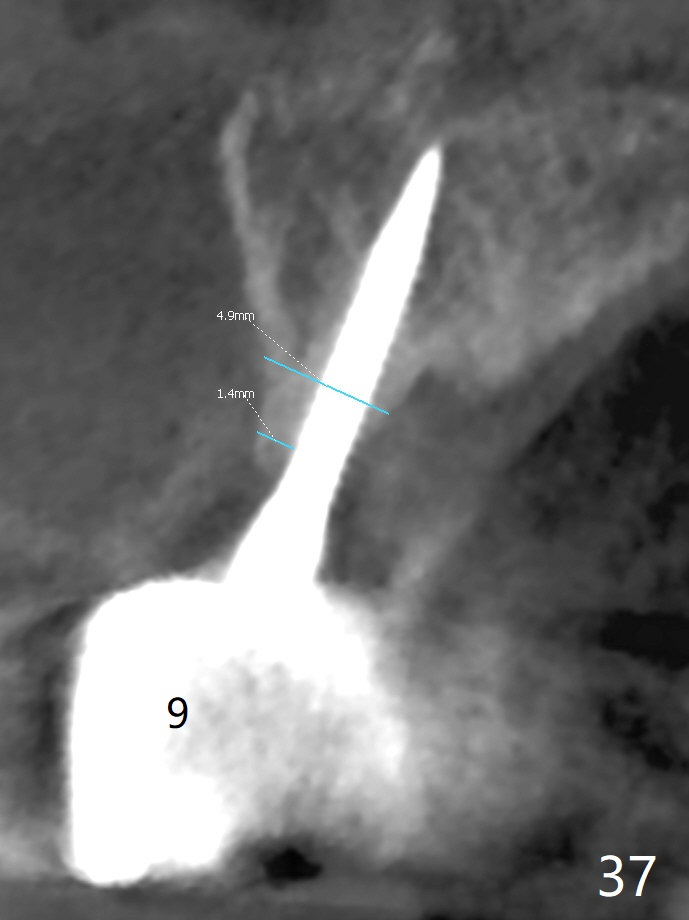

The implant at #8 fractures 1 year 4 months post cementation (2 years 2 months postop, Fig.35-41). All of the implants except #10 are placed in the middle of the alveolus.